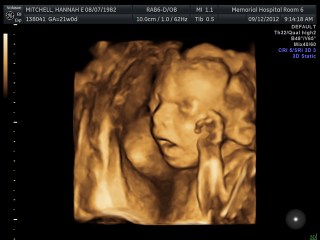

This entire pregnancy I have been doing battle with my thoughts… choking back fear, trying to rest in knowing that God created this to be just what He wanted, and that we won’t be disappointed. Some days I have been overwhelmed when the “what if’s” creep in, but overall with the constant support and reassurance of my wingman and dearest friends, I have been able to watch days blossom into months with growing reassurance that our unborn son will be sustained with life and good health.

In the crush of contractions, the peril of bleeding, Mark and I did our best to point out the positive…. Baby’s heartbeat is steady, he is getting the steroids for his lungs, the magnesium to prevent brain bleeds… soon the IV’s will stop the contractions. History won’t repeat itself. I held myself together… until the nurse confirmed my water had broken. That was it. All the panic and fear and struggle to be able to control life and death came screeching to the forefront of my thoughts.

In spite of myself, the sun came up again. A nauseating blend of medications has pushed us back from the edge of danger, and the tiny little legs and arms continue to jostle and roll within my swollen belly. Hope has taken root again, and faith dares to smooth the disrupted waters.